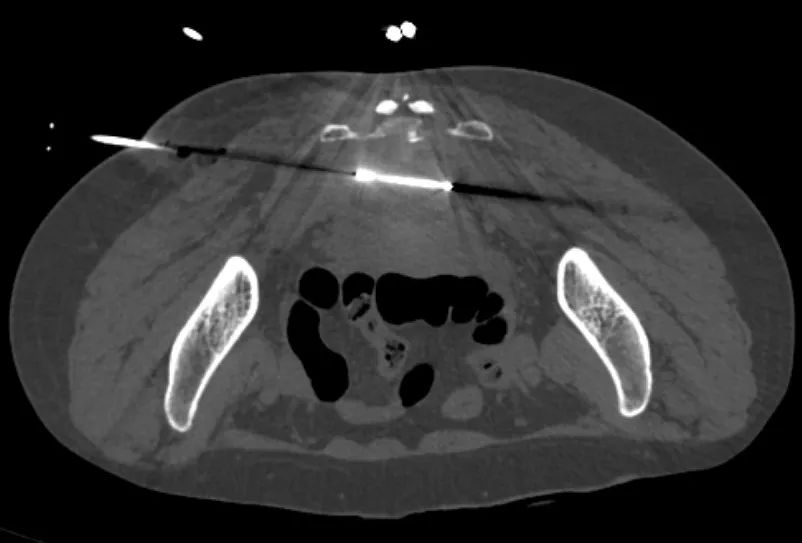

肛管癌骶部转移冷冻消融术术中的医学影像图片